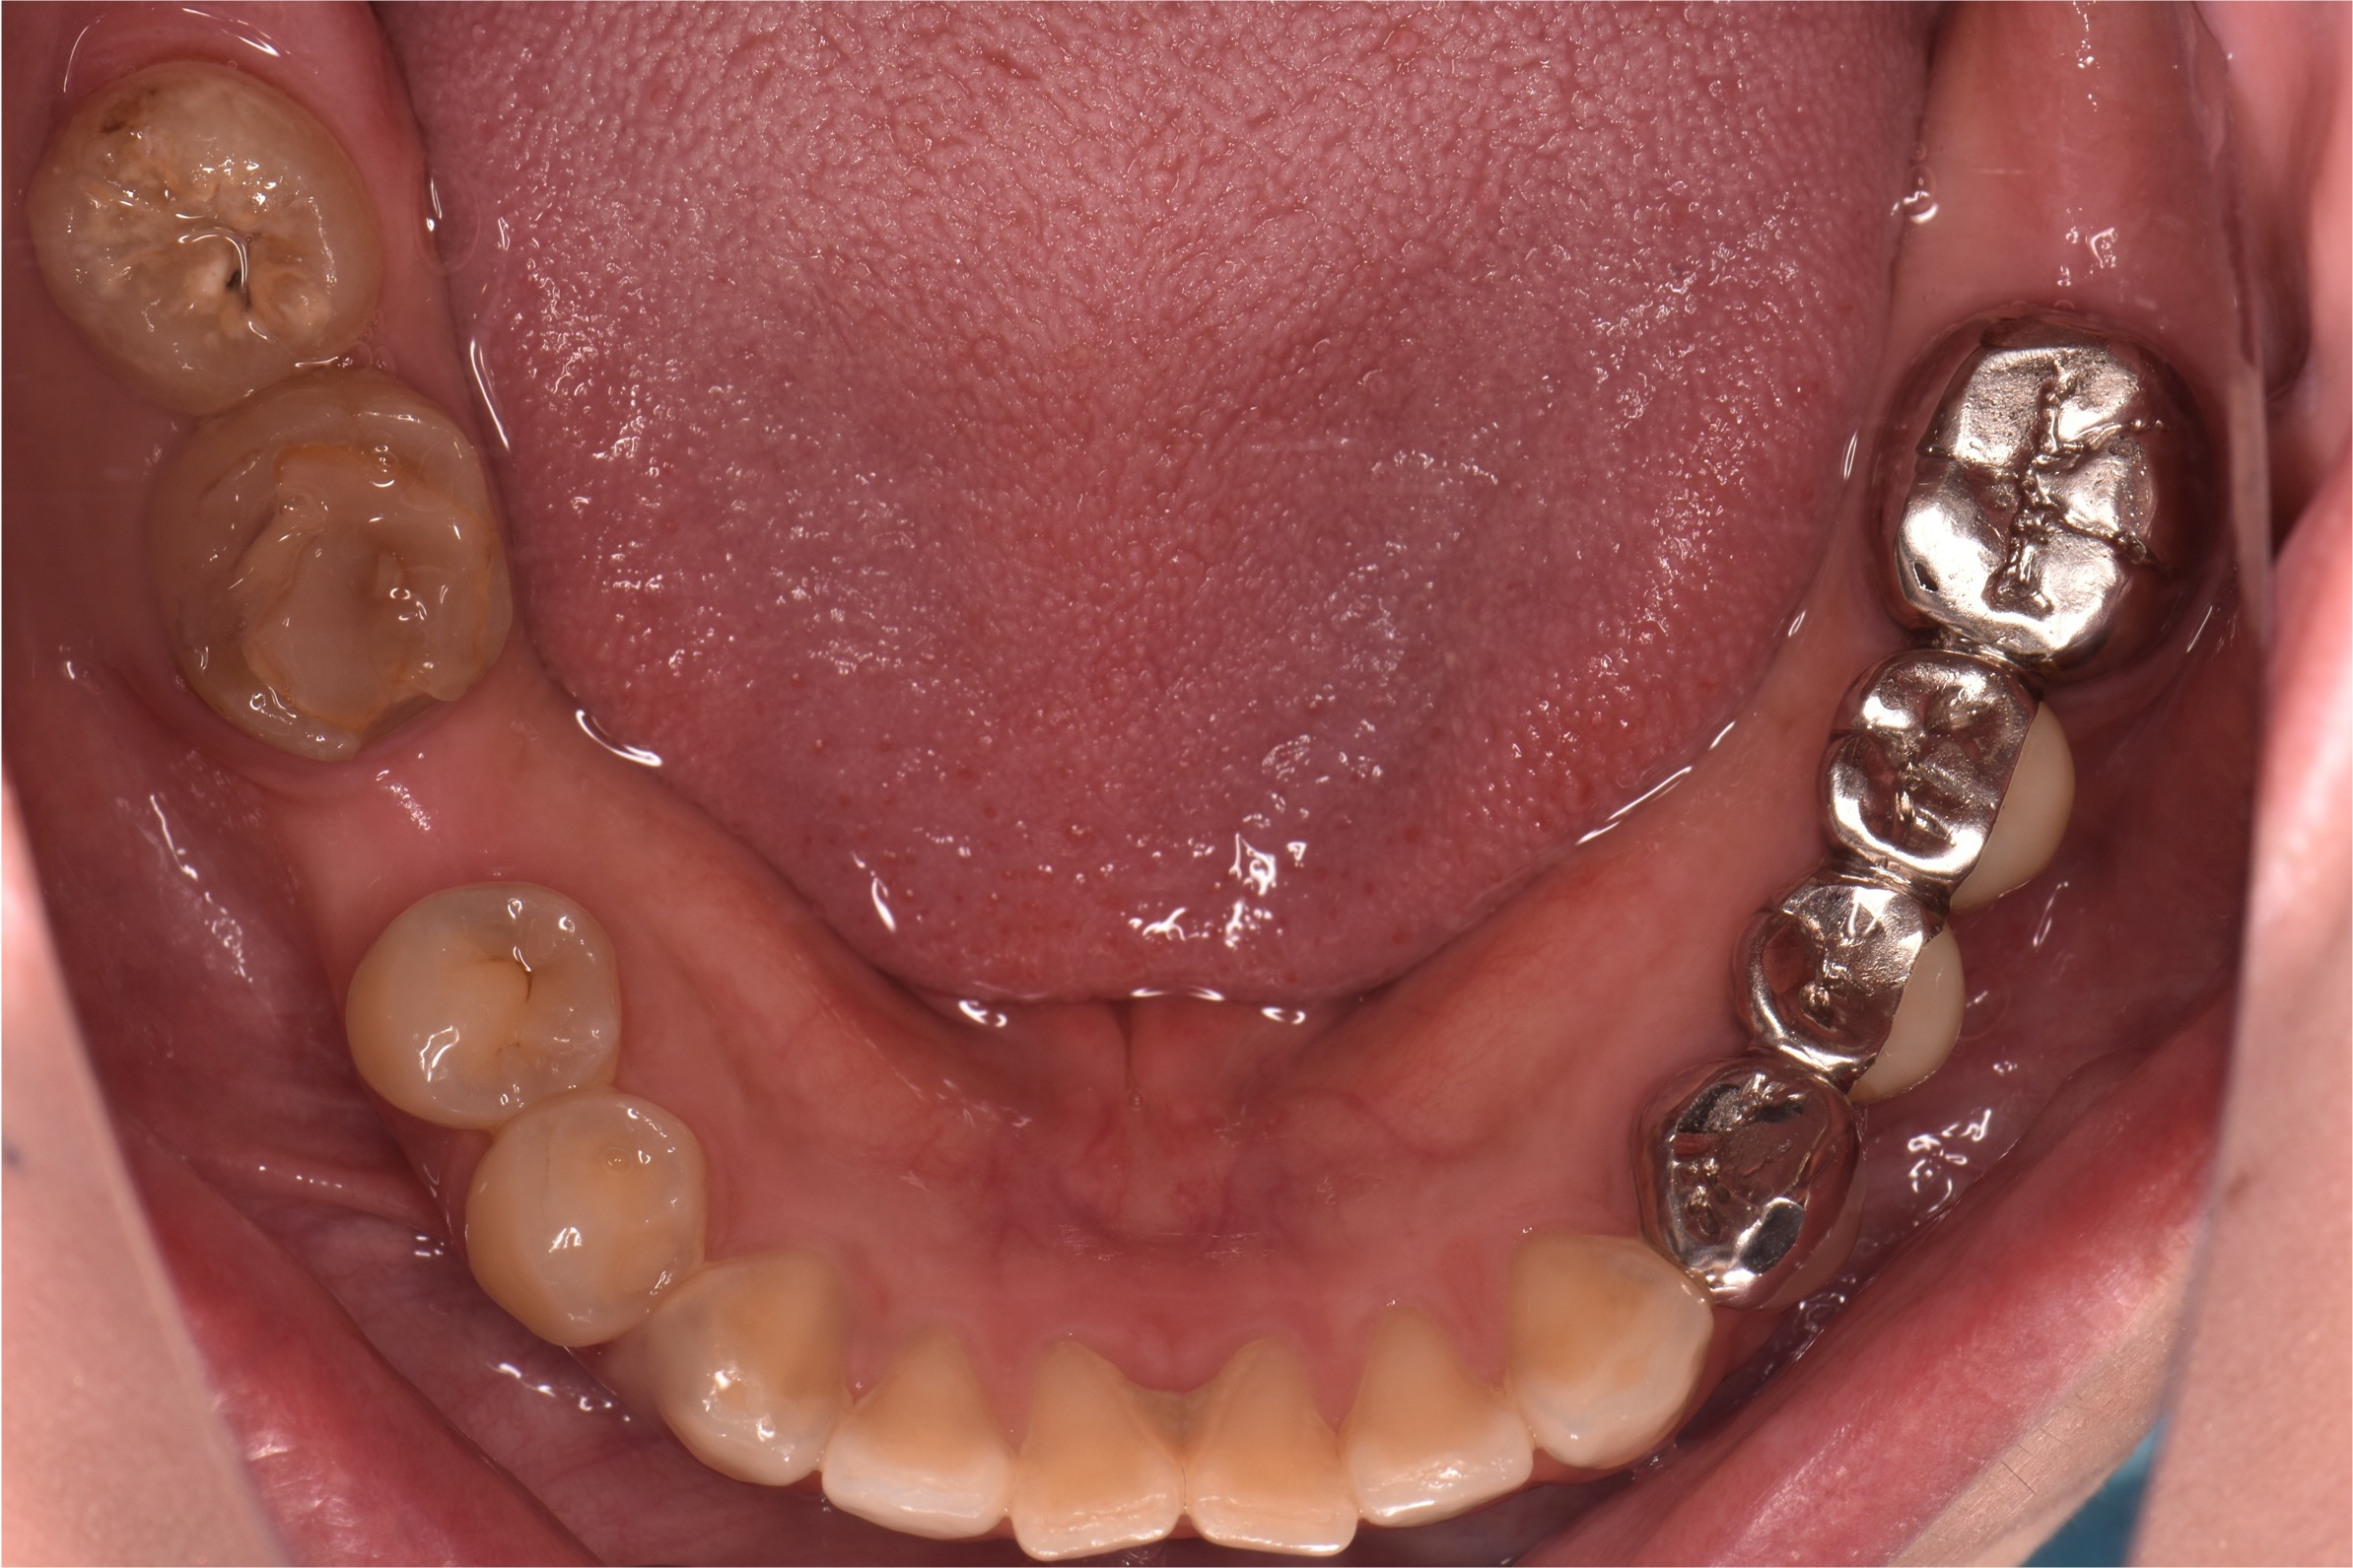

治療前

治療後